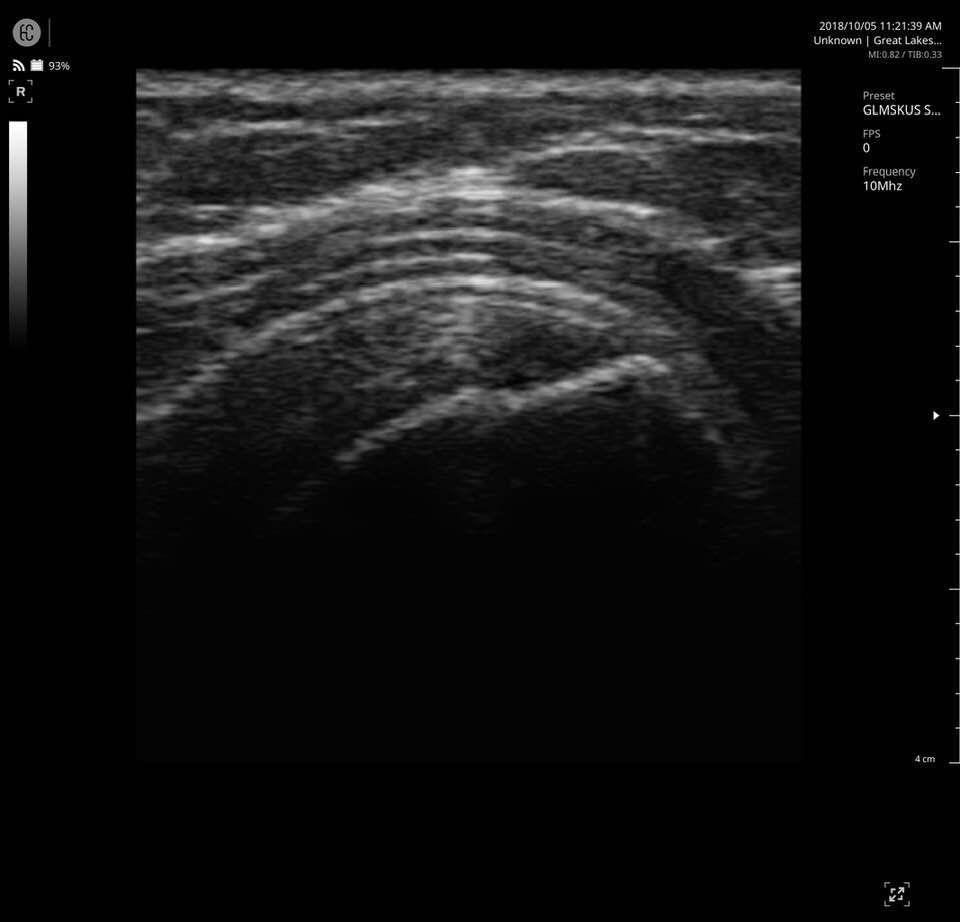

The SONON 300L transducer has cutting-edge technology and its software, combined with a proprietary sensor, turns any mobile device into a mobile ultrasound monitor with the same image quality and knobology as a traditional US machine. Software includes individual preset settings for your most common test.

- MSK

Specifications for SONON 300L:

- Multi-frequency: 5MHz 7.5MHz 10MHz

- Depth: max 10cm

- Field of View: 40mm